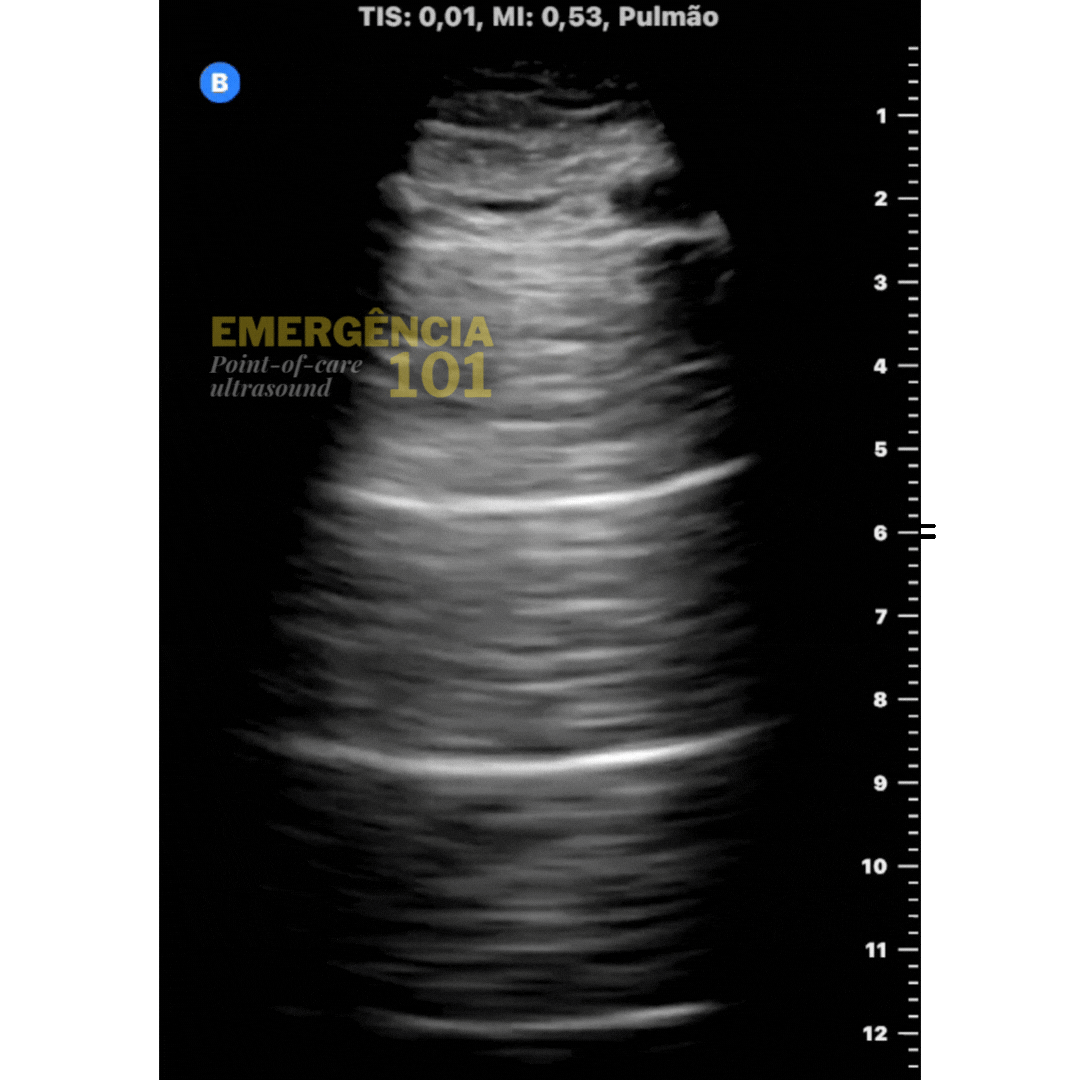

Figura 4a. Janela pulmonar normal, presença de linhas "A" (artefatos horizontais) com deslizamento pleural presente indicando pulmão aerado. Acervo pessoal do autor.

Figura 4b. Linhas B patológicas em um paciente com edema agudo de pulmão. Perceba que as linhas B acompanham o deslizamento pleural. Acervo pessoal do autor.

Figura 4c. Linhas C secundárias à pequenas consolidações subpleurais em paciente com pneumonia. Perceba a semelhança do artefato vertical com as linhas B, porém com uma linha pleural mais irregular e espessada. Acervo pessoal do autor.